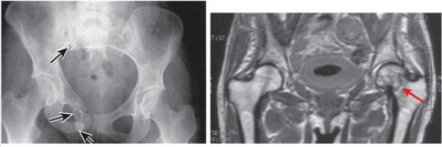

What is the difference between Coxa Vara and Coxa Valga?

Coxa Vara and Valga are the angle of inclination between the long axis of the femoral neck and the femoral shaft